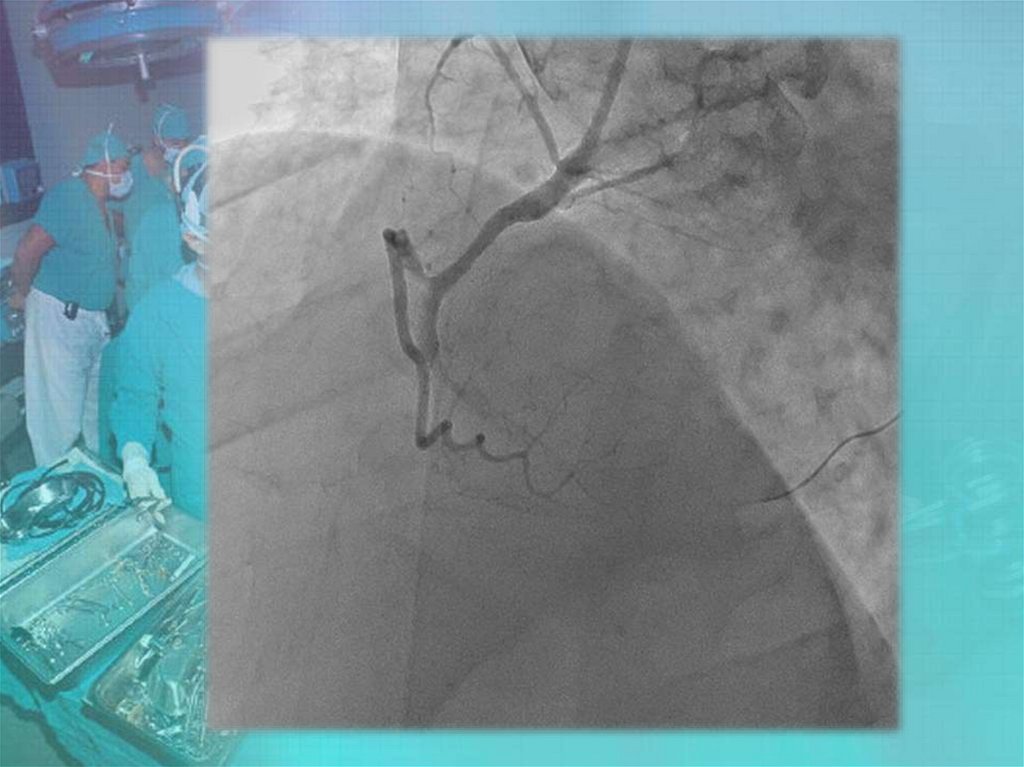

Коронары. СНК кафедры факультетской хирургии №2 лечебного факультета

СНК кафедры факультетской

хирургии №2 лечебного

факультета